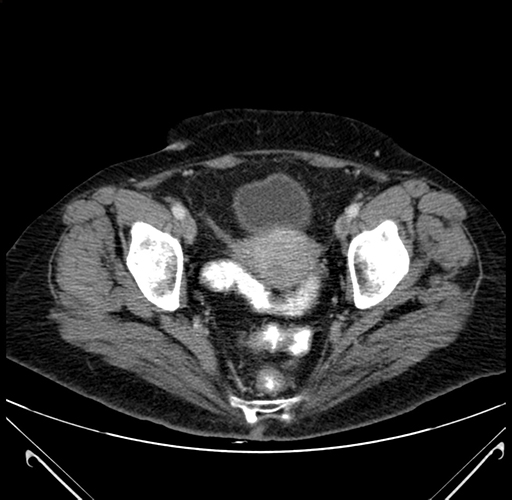

Axial Venous

Coronal Venous